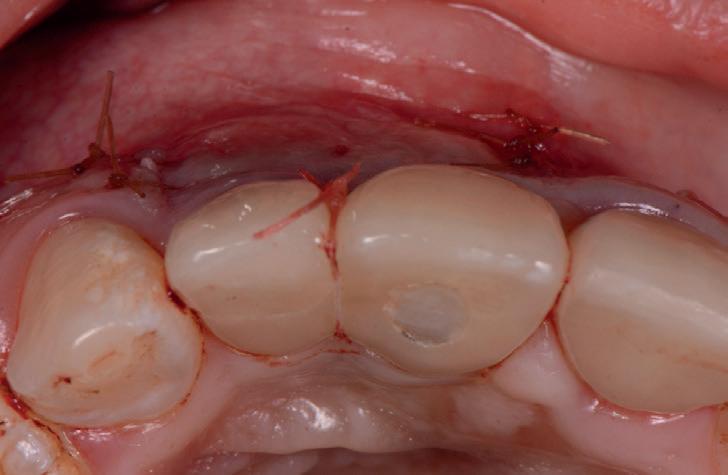

RECONSTITUIREA țesuturilor moi periimplantare. Scopul acestui raport de caz este de a demonstra procedurile chirurgicale utilizate pentru corectarea unui defect al țesuturilor moi periimplantare folosind țesutul moale interdentar în combinație cu tuberozitatea ca locație donatoare de țesut conjunctiv, utilizând o abordare prin tunelizare într-o zonă estetică.